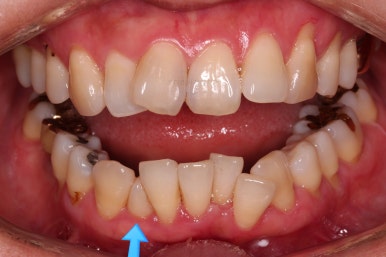

비밀은 바로 화살표에 있습니다.

유치 잔존

말그대로 어릴 때 빠져야 할 유치가 남아있다는 뜻인데요.

앞니 사이에 뾰족하게 남아있다 보니 자리만 많이 차지하고 있는 모습이었고 다른 영구치를 더 삐뚤게 만들었어요.

딱히 영구치가 모자라진 않는데 유치가 잔존하는 굉장히 드물고 독특한 상황이었습니다.

당연히 유치는 뽑기로 했고요.